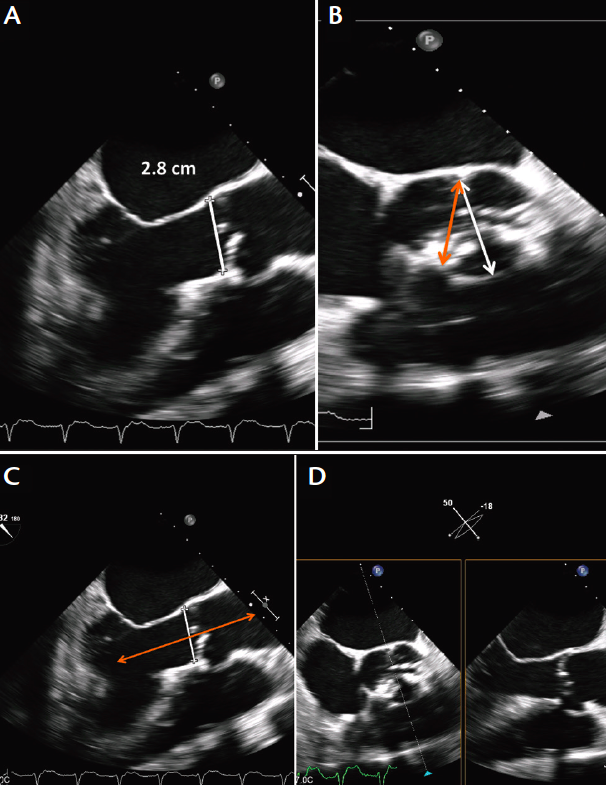

TAVI Work - Up

Transthoracic Echo

Transesophageal Echo

- Annulus dimensions

CT Coronary

- Aortic annulus dimensions

- Aorto-Iliac peripheral arterial disease

-Distance between coronary ostia and aortic annulus

Angiogram